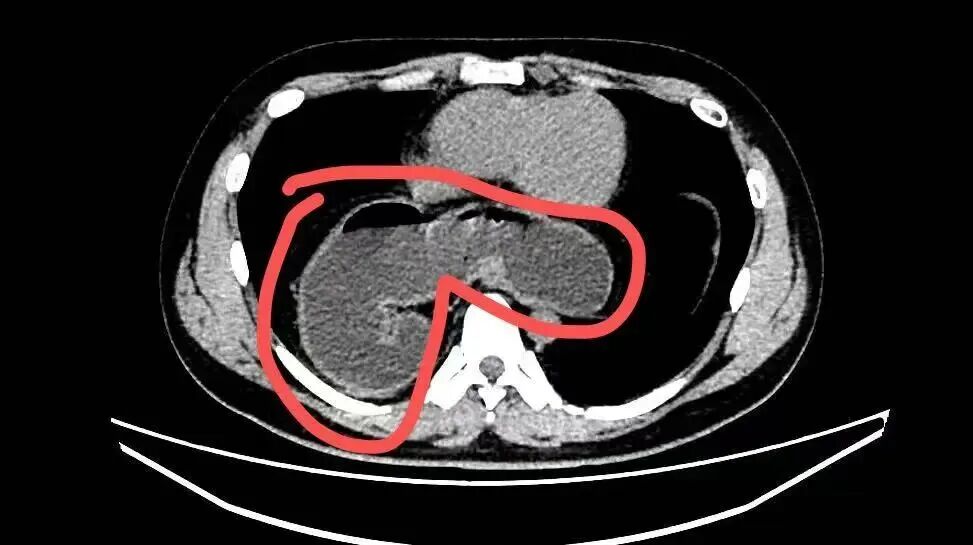

日前,周太成接诊一位自述经常感觉消化不良的患者。林先生(化名)28岁,长期被反酸、嗳气、烧心等症状困扰,一直以为只是普通胃病,不舒服就去消化内科开药,每次吃药都有所改善,每年全身体检也并未发现异常,因此没进一步排查。直到去年10月,因为咳嗽不止并出现迁延不愈的肺炎,林先生在当地医院就诊,肺部CT检查中发现:一部分的胃竟然“跑”进了胸腔里!

影像资料显示,小伙子的部分胃通过食管裂孔疝“逃跑”至胸腔。